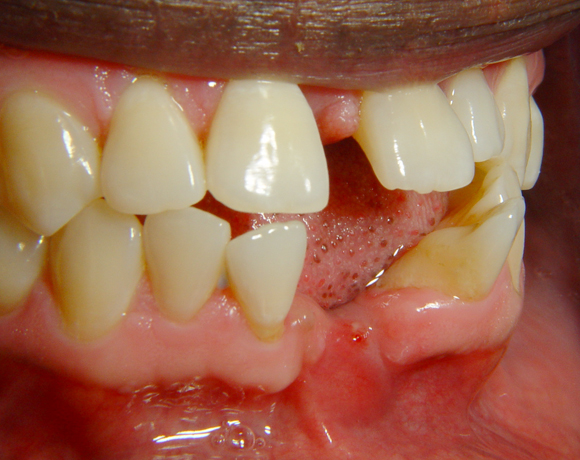

Diese Frontzahnsituation stellte den Behandler vor größere Probleme

Durch Abrasion der Seitenzähne wurden die Frontzähne nach labial verdrängt und lückig. Nach Verlust des Zahnes 41 entstand eine Lücke in der drei Zähne Platz fanden. Auch im Oberkiefer wurden die lateralen Lücken mit Veneers verkleinert.